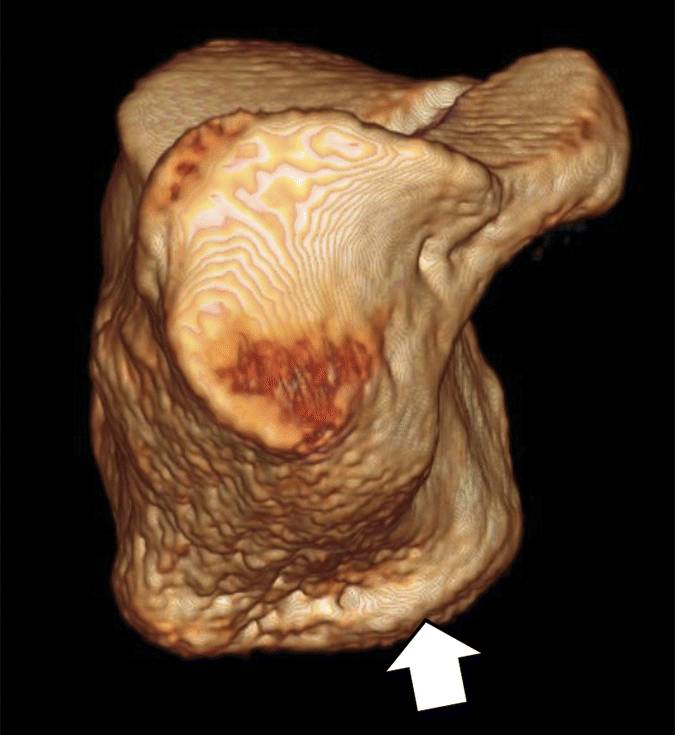

图5A-内侧足底过程的图像。A,在尸体中的跟骨的正面3D CT图像显示内侧足底过程(箭头)的板状突出,。